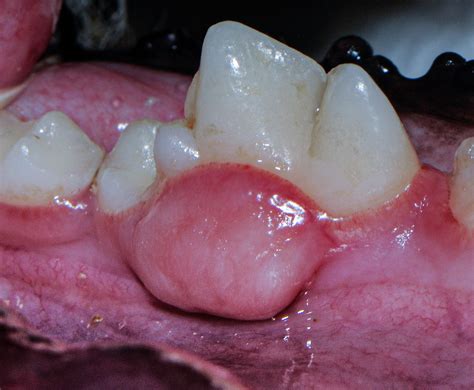

Symptoms of Cancerous Jaw Tumors

The symptoms of a cancerous jaw tumor can vary depending on the location and size of the tumor. Common symptoms include:

• Persistent pain or swelling in the jaw

• Loosening of teeth

• Difficulty chewing or swallowing

• Numbness or tingling in the jaw or face

• Swelling in the neck